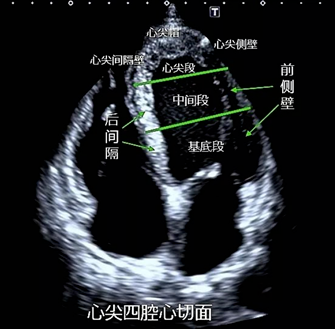

心尖四腔心、二腔心、三腔心切面也可用于观察室壁运动情况。

心尖四腔心观察左室基底及中间部下间隔、侧壁节段,心尖部间隔、侧壁节段